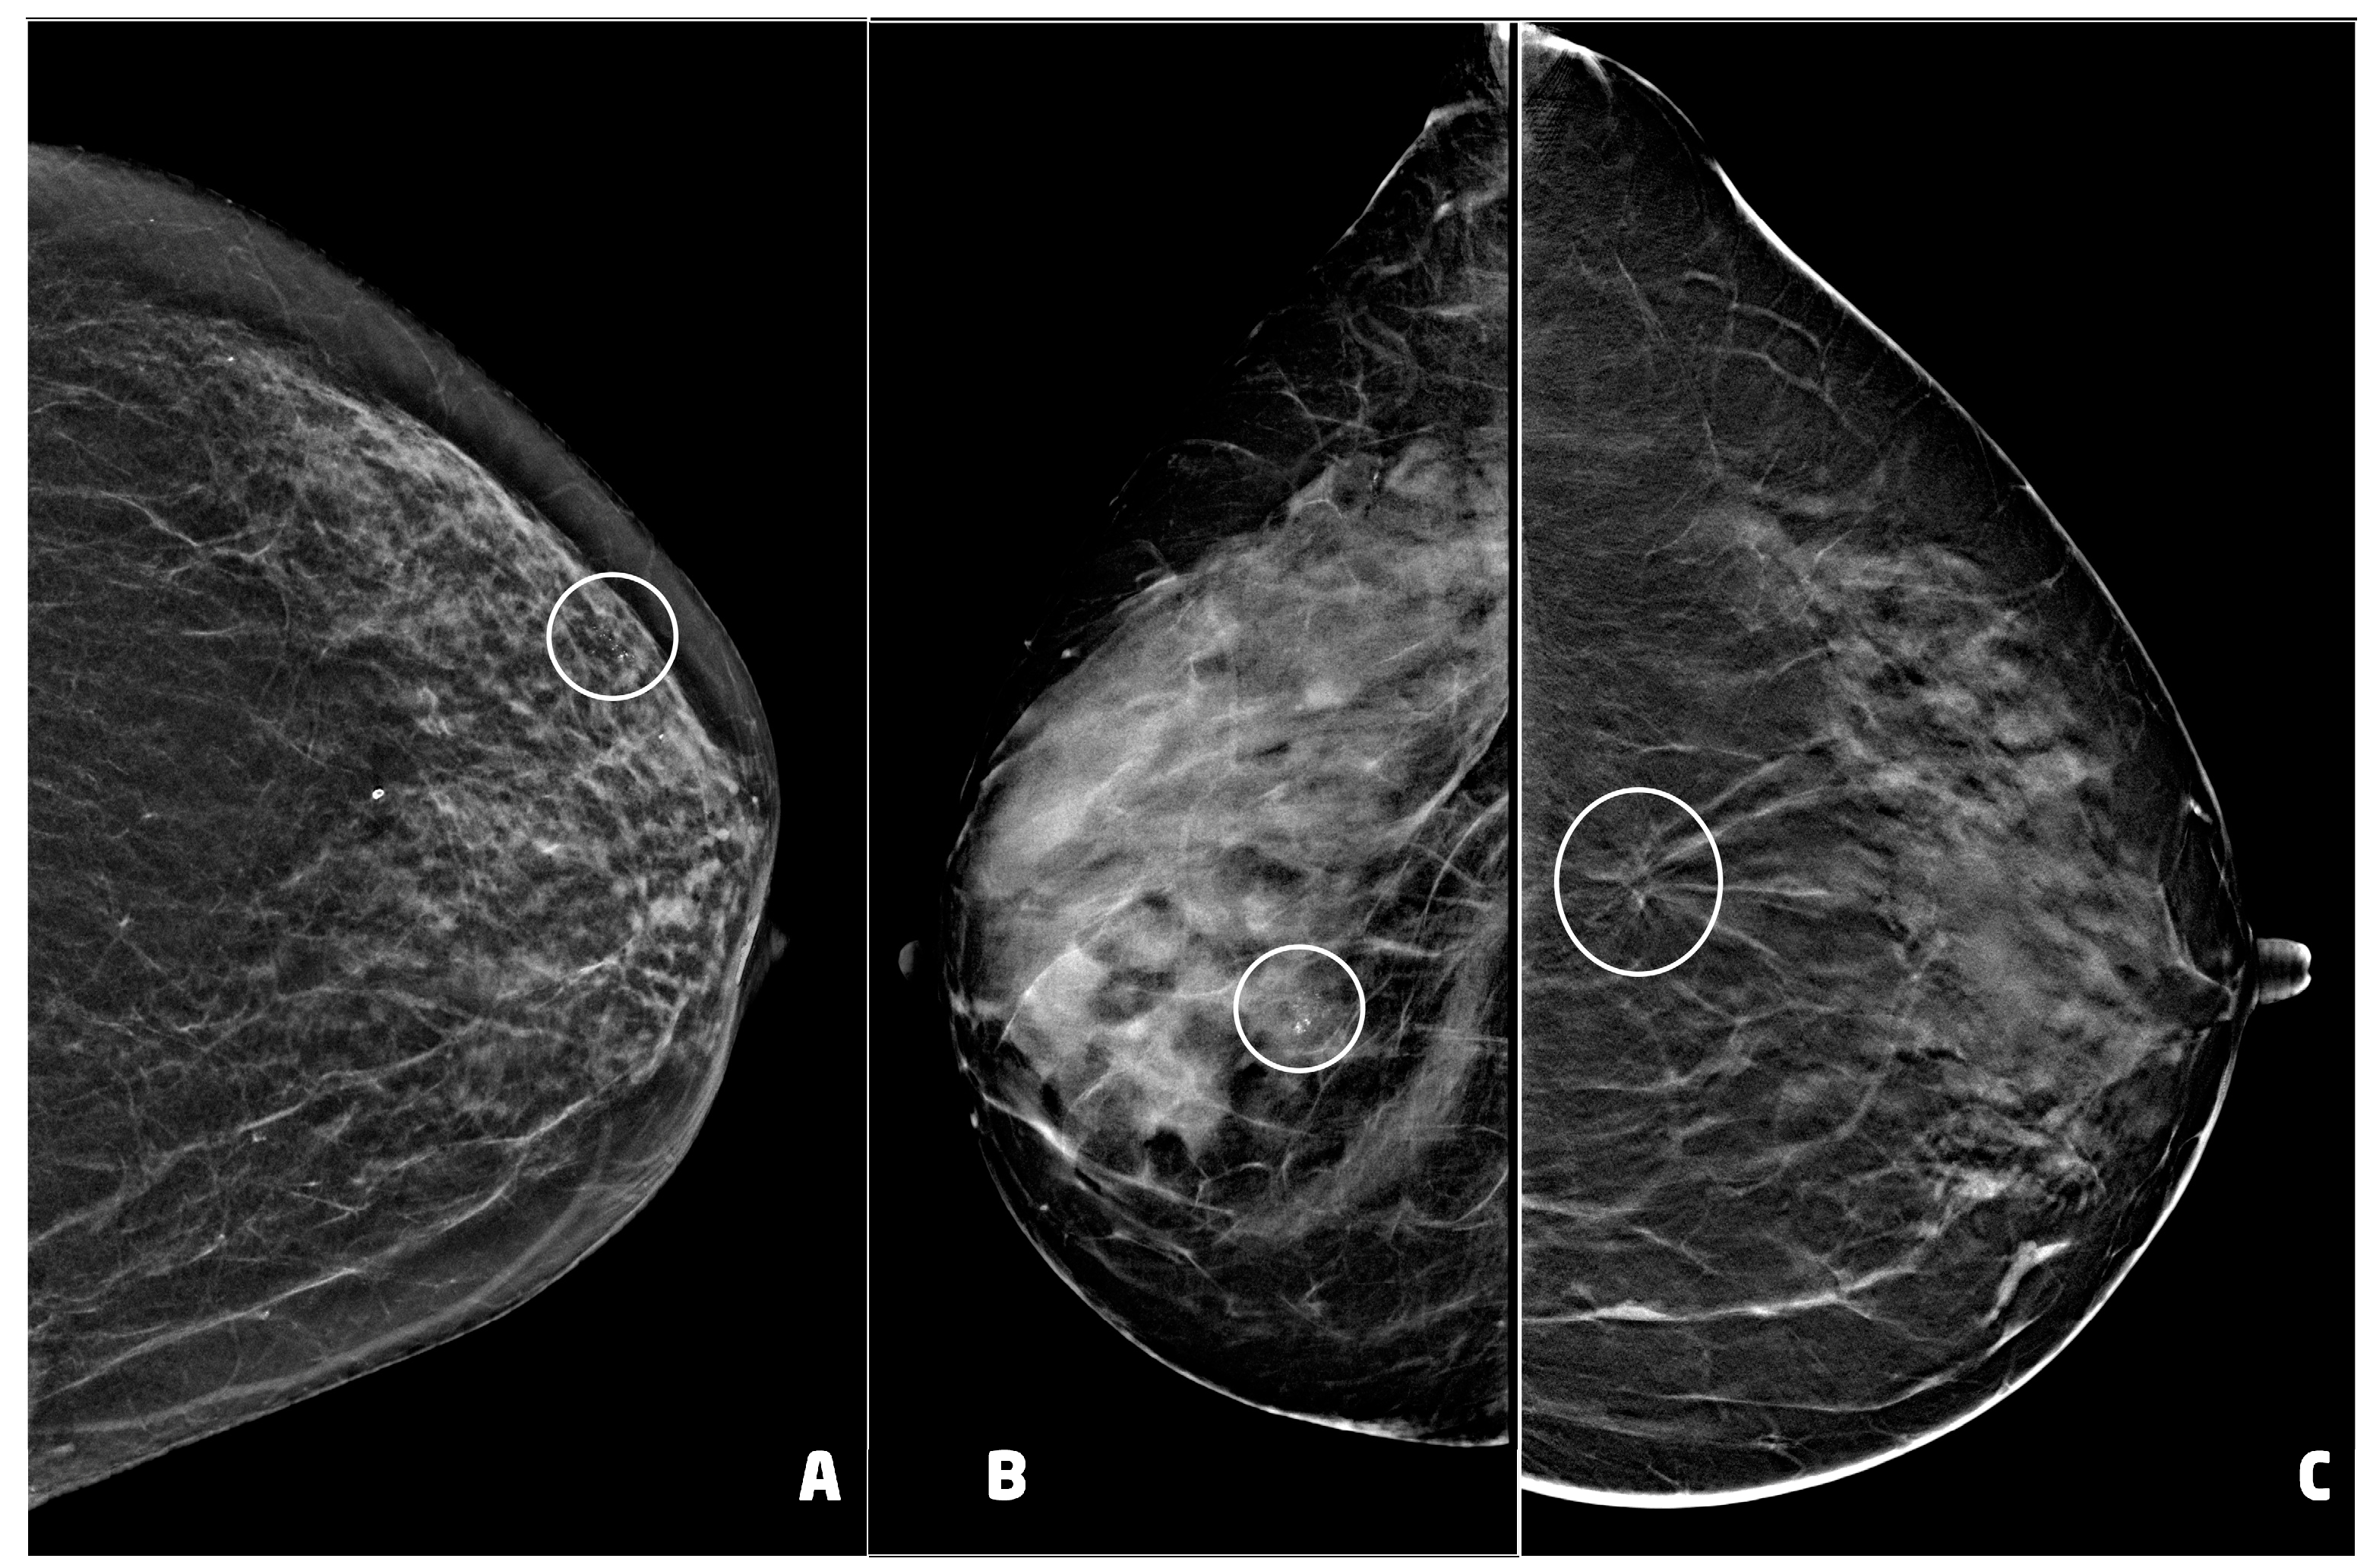

Thirty (30) BC presented as microcalcifications with (four) or without (26) architectural distortion. Six (6) BC presented as architectural distortion without microcalcifications, and one BC presented as an inhomogeneous area of asymmetrical density with scattered microcalcifications (Figure 4). Of the 37 BC diagnosed, 26 were in stage 0 and 11 in stage IA (Table 1).

Figure 4. Examples of suspicious non palpable lesions undergone VABB: (A) 66 year-old woman, 2D synthetic view of the left breast showing a cluster of microcalcifications at the upper outer quadrant, in periareolar region (circle), ductal carcinoma in situ, G1; (B) 53 year-old woman, 2D-FFDM view of right breast showing a cluster of microcalcification in the equatorial region (circle), ductal carcinoma in situ, G3; (C) 55 year-old woman, 2D synthetic view of the left breast showing an area of architectural distortion at the union of the upper quadrants (circle), invasive ductal carcinoma, tubular variant.